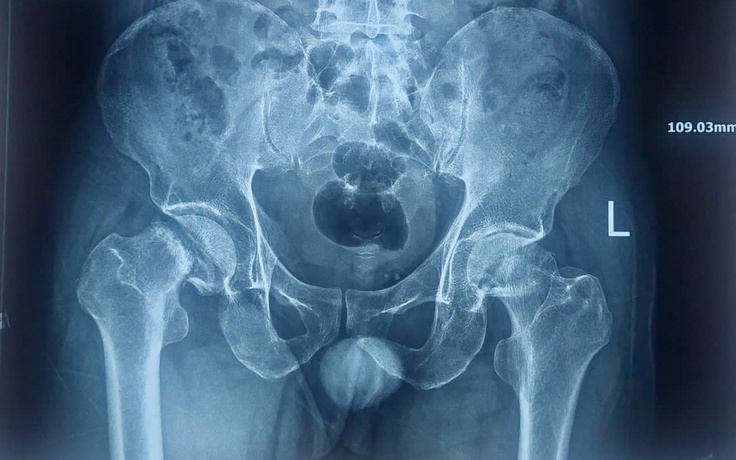

Nam bệnh nhân bị đau khớp kéo dài nhiều năm, đi bệnh viện khám mới phát hiện bị hoại tử xương 2 bên khớp háng. Nếu không điều trị kịp thời, bệnh có thể tiến triển đến tàn phế.

Đau khớp háng, khởi phát của hoại tử chỏm xương đùi